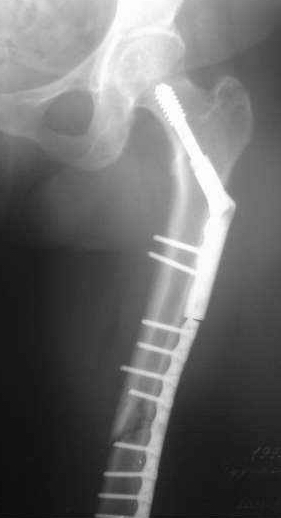

Уважаемые коллеги, пердлагаю к обсуждению больную 50л. Оперирована 4 июня 2006г авф.

На сегодня - состояние консолидации представлено на рентгенограммах. Имеется ли целесообразность реостеосинтеза интрамедуллярным гвоздем? Все зависит от пожелания больной? Чего хочет больная пока не спрашивал, поскольку никто в отделении не согласилсядаже с относительным показанием к интрамедулярному реостеосинтезу. Нужна ли коррекция оси б/берцовой кости? Хотелось бы услышать ваше мнение. Спасибо.

??? деформация (судя по снимкам) минимальная и некритичная. На штифте должно все исправиться.

> Нужна ли коррекция оси б/берцовой кости?

Надо ее для начала оценить - сделать снимок со смежными суставами, такой же - второй голени, потом использовать последний как шаблон.

Если отклонение сочтете клинически значимым, то изменить ось можно и сейчас в аппарате, и при штифтовании, используя отклоняющие (Poller) винты или лучше спицы.

на мой взгляд, консолидация достаточна для проведения пробы в аппарате, а ось вполне удовлетворительна.

по результатам пробы-остеосинтез ( или нет)

Антон, сделано-то ведь оччень не плохо. Что побуждает говорить о реостеосинтезе? Сроки? А Вы клиническую пробу(покачивание при раслабленных стержнях проводили? Мне кажется, что консолидация неплохая. Можно снять аппарат и 3 - 4 недели в У-образной лонгете. Обычно очень хорошая мозоль появляется.

Уважаемый Антон, на мой взгляд, есть реальная опасность развития ложного сустава большеберцовой кости (учитывая сроки и некоторые рентгенологические признаки - последнее не факт!). "Поиграть" на аппарате не получится - не даст малоберцовая кость. Предлогаю более "бюджетный" вариант: через небольшой разрез провести остеопериостальную декортикацию большеберцовой кости в области перелома. Фиксация аппаратом еще на 1.0-1.5 месяца, обязательная нагрузка на оперированную конечность. При условие "спокойных" спиц аппарата. А по поводу "чего хочет больная": врач предлогает - пациент выбирает.